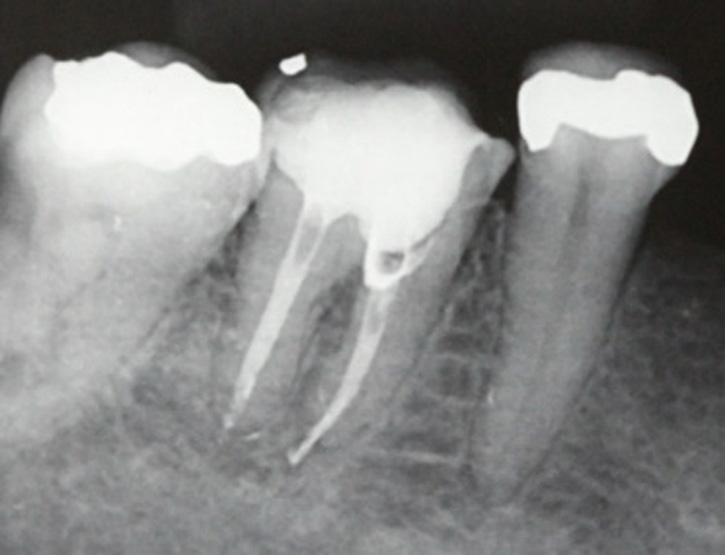

Tooth #11 with a calcified canal following traumatic injury